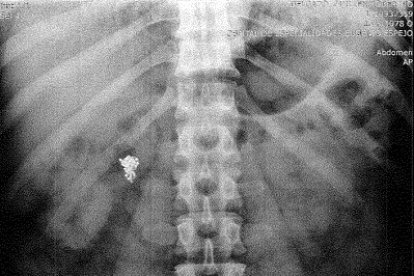

El médico Patricio Castillo analizó la radiografía en la que se muestra que el objeto permanece en el interior del intestino del sospechoso. Considera que, por el momento, no existe obstrucción. Por ende, según él, se puede evacuar.

Sin embargo, el experto enfatiza que si no se extrae podría presentarse algún tipo de infección. Para sacarla, entonces, tendrían que hacerle una limpieza intestinal y una aspiración nasogástrica. “Luego se debería tratar con medicamentos por el riesgo de infección”.